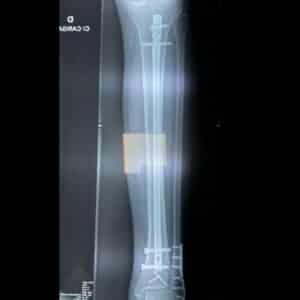

Tratamento Cirúrgico vs. Conservador:

O tratamento de fraturas da perna pode ser abordado de duas maneiras principais: conservador (não operatório) ou cirúrgico. A escolha entre esses métodos depende de vários fatores, incluindo o tipo e a localização da fratura, a idade e a saúde geral do paciente, e a complexidade da lesão. O tratamento conservador geralmente é preferido para fraturas simples e estáveis, onde os ossos não se deslocaram significativamente.

Nas fraturas mais graves ou complexas, o tratamento cirúrgico pode ser necessário. A cirurgia podeenvolver a fixação interna, onde placas, parafusos ou hastes intramedulares são usados para manter os ossos no lugar. Em casos de fraturas expostas ou cominutivas, uma limpeza cirúrgica e o uso de fixadores externos pode ser necessário para estabilizar a lesão enquanto os tecidos melhoram sua condição. A escolha do método cirúrgico depende da natureza da fratura e da experiência do cirurgião, mas ambos os métodos visam realinhar os ossos e promover uma recuperação eficiente.